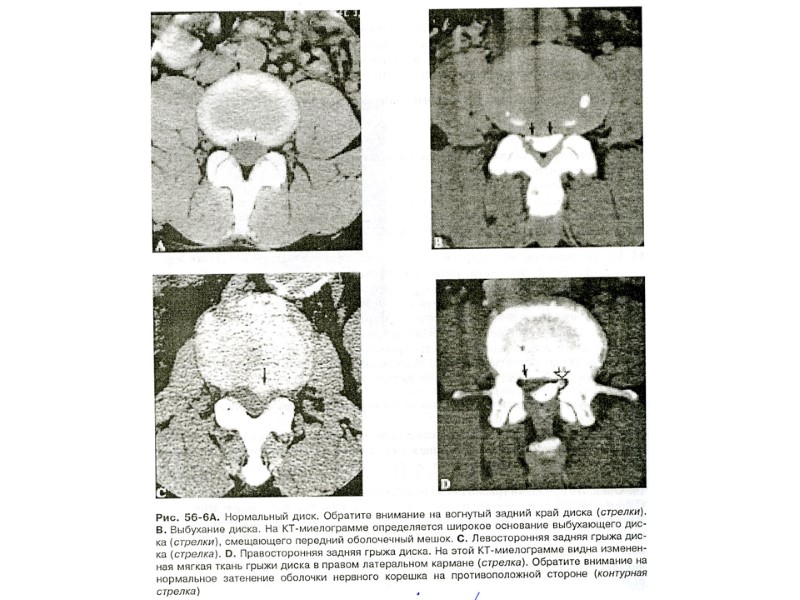

Рентгенологические симптомы Расширение рентгеновской суставной щели Сужение рентгеновской суставной щели Склероз субхондральных пластинок Продуктивные изменения по краям суставной поверхности Узурация суставной поверхности Патологические подвывихи Изменения суставов